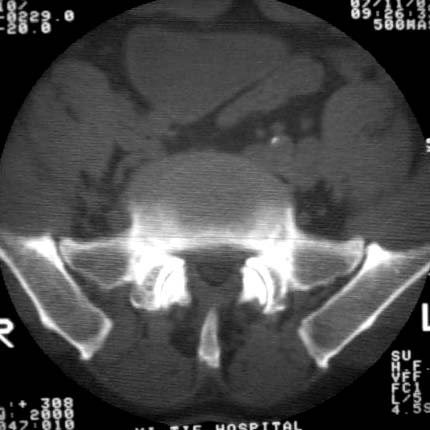

男57岁,腰痛,双腿麻木,请各位老师帮忙看看箭头所指是什么?ct值约900-1000hu是钙化影吗?

双侧髂总动脉钙化.

是右侧髂总动脉壁粥样硬化斑钙化,左侧亦有。

退行性骨关节病。